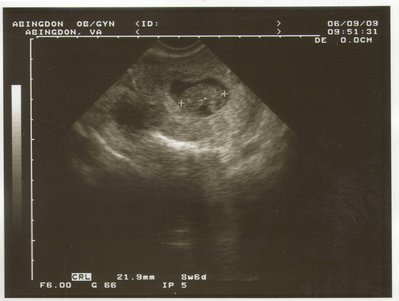

Татиана писал(а): Ой, ну как сказать: когда я своего ребенка увидела в 8 недель с ручками и ножками и сердебиением-то рыдала. А в 17- я уже делала 3д фотки: там человечек с личиком и щечками. Мне даже было страшно подумать, если что пойдет не так. в 8 недель? у меня, наверное, нет воображения совершенно... мож, поэтому и не рыдала Natiii, махнемся? я так мальччика хотела, а УЗИ показало девочку.

| Вложения: |

BabysFirstPic.JPG [ 316.26 КБ | Просмотров: 2567 ]

Похоже, и у меня воображение отсутствует  Я вот тоже удивилась, как в 8 недель Татьяна ручки-ножки умудрилась рассмотреть  Мы в 8 недель делали - да, серцебиение увидели, но никакие части тела и близко определить невозможно было... на этом сроке размер плода не больше 2 см. Ань, а эта фотка на каком сроке?

Хочу поделится фото моего малыша! Удивительно- он говорит ХАЙ всему миру. 13 недель срока